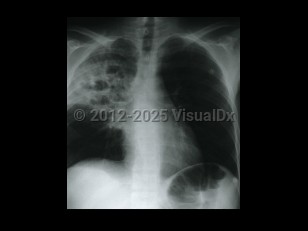

Rhodococcus equi is an obligate aerobic, asporogenous, non-motile, gram-positive rod (coryneform bacteria) that can appear bacillary in liquid media and coccoid on solid media. It is named after the salmon-pink to red mucoid colonies (red coccus) that it forms on solid media and was originally thought to be solely a veterinary pathogen primarily found in foals. It was not described in humans until 1967, when it was seen in an immunocompromised patient who presented with fever and a cavitary lung lesion.

Typically, patients present with pulmonary disease with a subacute course. Main complaints include cough (productive or non-productive), fatigue, fever, and sometimes pleuritic chest pain. Hemoptysis has been reported in 15% of cases. Rhodococcus equi bacteremia frequently complicates pneumonia. Other complications may occur: lung abscess, endobronchial lesions, pleural effusion, empyema, pericarditis, cardiac tamponade, and mediastinitis. Upper lobe cavitary and/or nodular disease is found on radiography, leading to frequent misdiagnosis of tuberculosis. This misdiagnosis can be further compounded by the occasional acid-fast positive stain of the organism. Infection in other locations is usually a late manifestation of pulmonary infection.